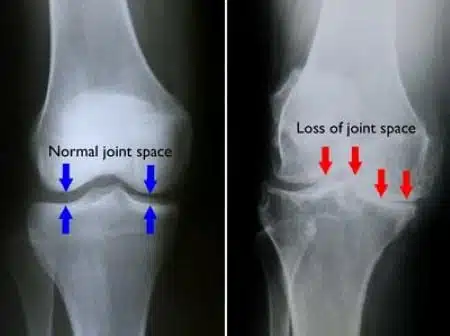

हड्डियों का घिस जाना—उम्र के साथ साथ हड्डियो का घिस जाना भी एक बड़ी समस्या होती है हड्डी तभी घिस जाती है जब हमारे शरीर में कैल्शियम की मात्रा बहुत ज्यादा कम हो जाती है और हड्डी जरा सी भी ठोकर लगने के कारण हमारी हड्डी इशारे से टूट जाती है ।